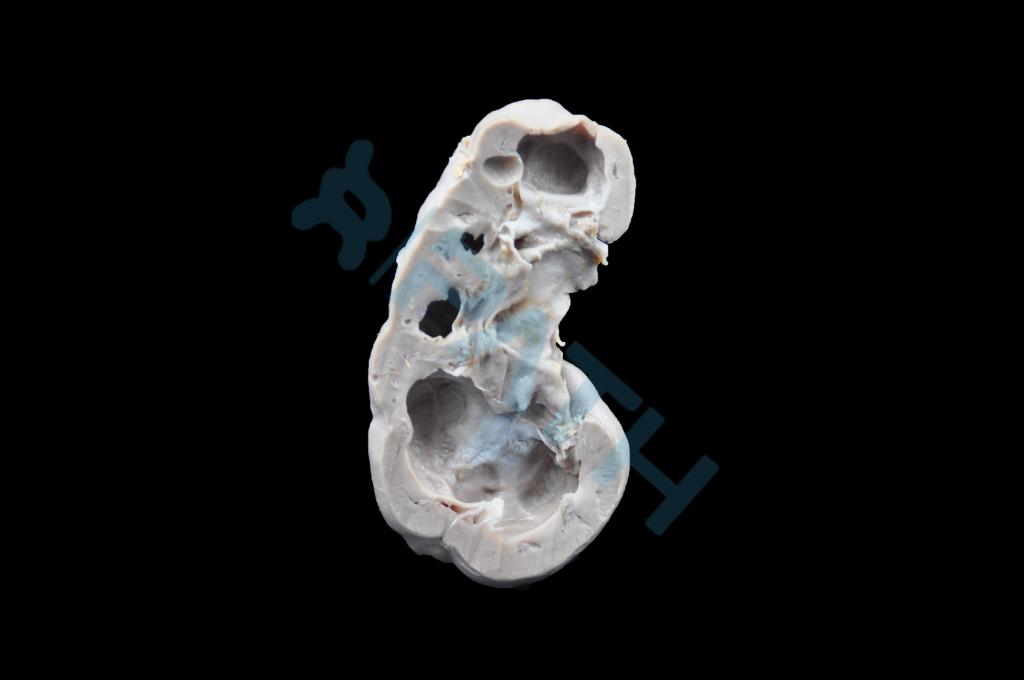

肾脏压迫性萎缩